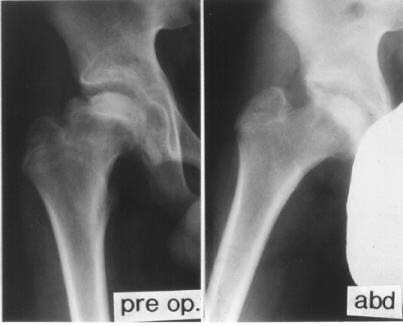

PREOPERATIVE PLANNING:

- Anteroposterior and true lateral radiographs should be performed.

For the true lateral radiograph, the patient should be positioned

supine, with the hip in precisely 90 degrees of flexion and 45

degrees of abduction and with neutral rotation.

- The preoperative lateral view radiograph shows the A-P view

of the femoral head as it will appear after 90 degrees of posterior

rotation.

- In contrast, a preoperative lateral view in a reversed position

shows the A-P view after 90 degrees of anterior rotation.